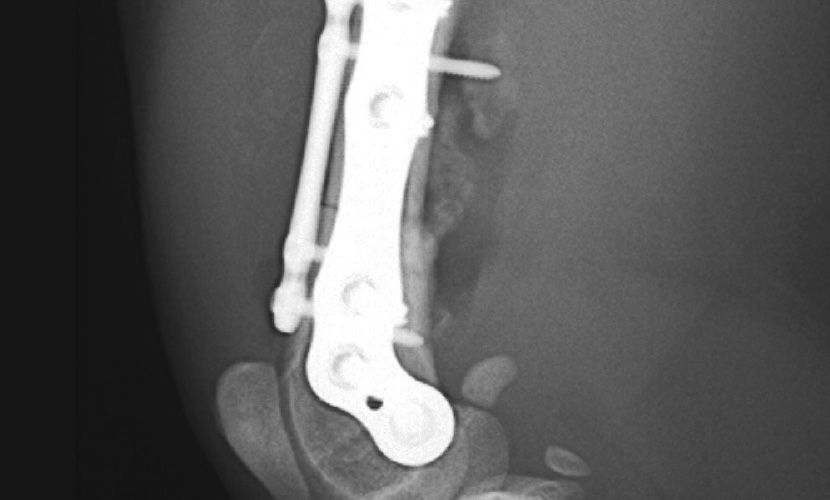

右大腿骨遠位横骨折 腹尾側変位

雑種猫 1歳 雄

Fixinダブルプレート(2.5mm、1.7mm)

術後10日で走り回る。